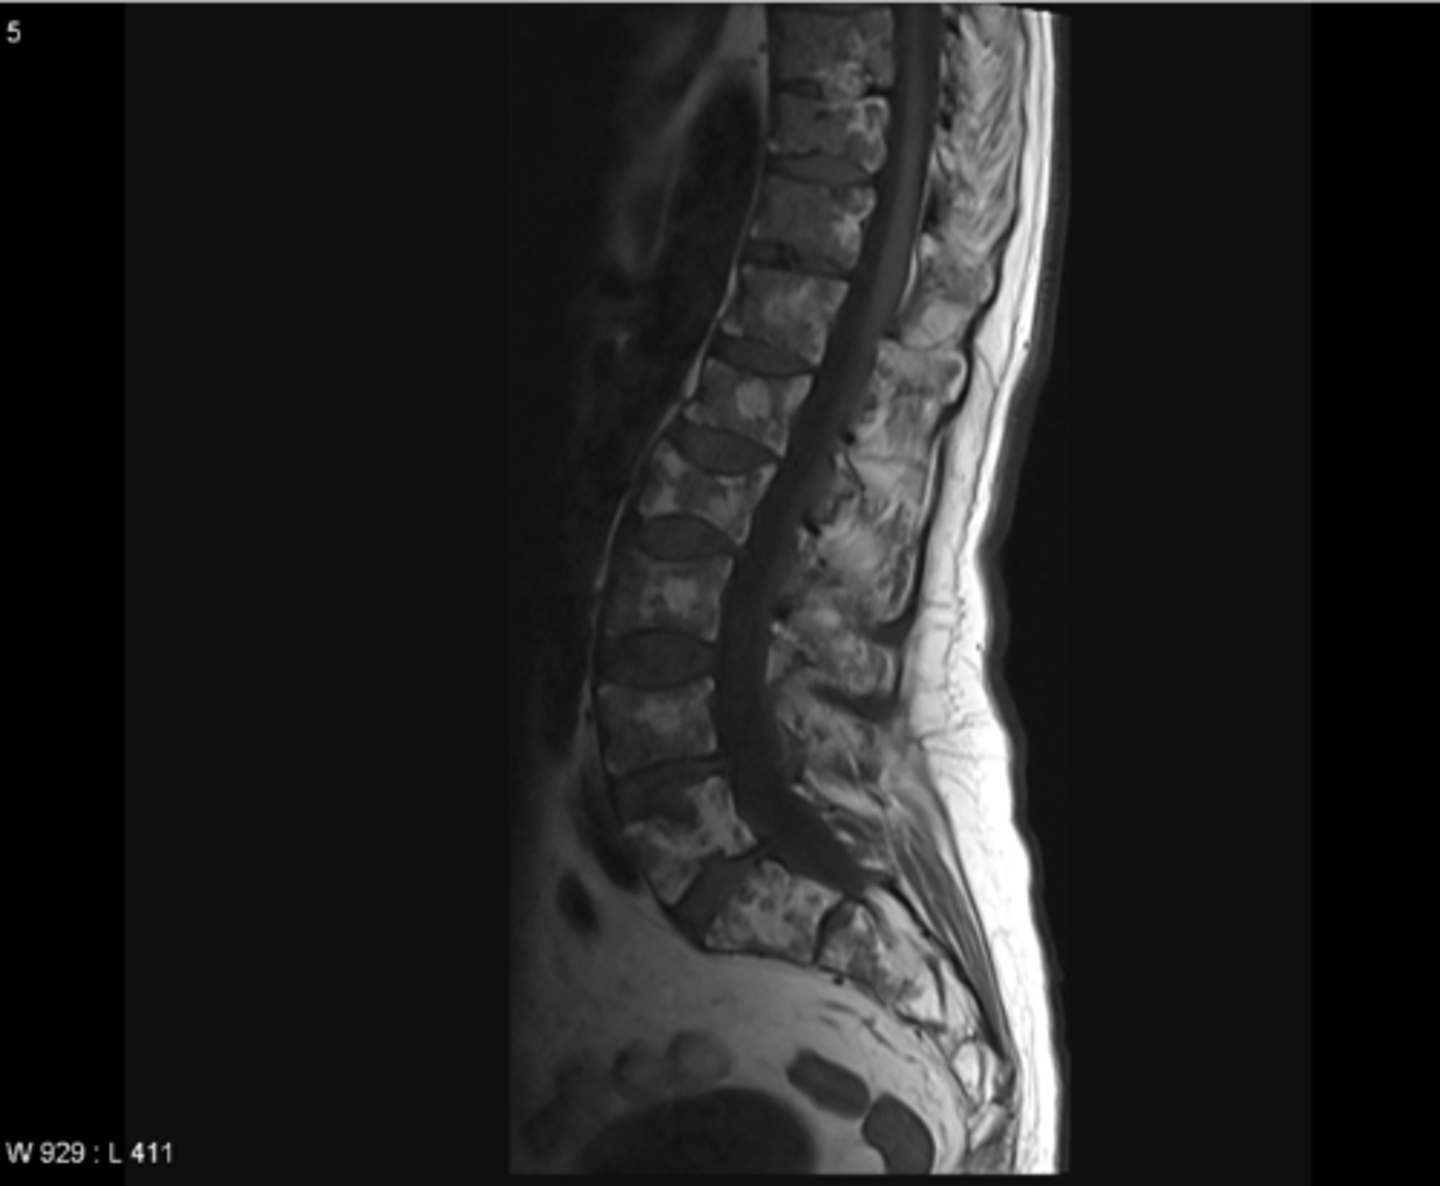

MRI head is most helpful in evaluating __________

soft tissue disturbances (tumors, brain infections, dementia, inflammation)

CT myelography can be used to evaluate the ____ and _____

spinal cord and canal

CT myelography is a good alternative to MRI to identify

spinal stenosis, disc herniation, spondylosis, arthritis

spinal stenosis

Narrowing of the spinal canal that causes pressure on the spinal cord (nerves)